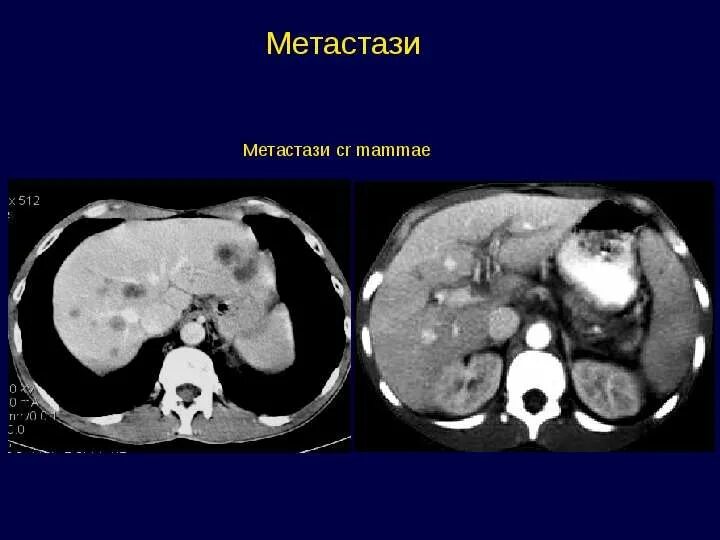

Метастазы у ребенка